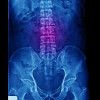

Radiologi lumbosacral AP, osteophyte l4-l5, lain2 dalam batas normal dengan kesimpulan spondylosis lumbalis